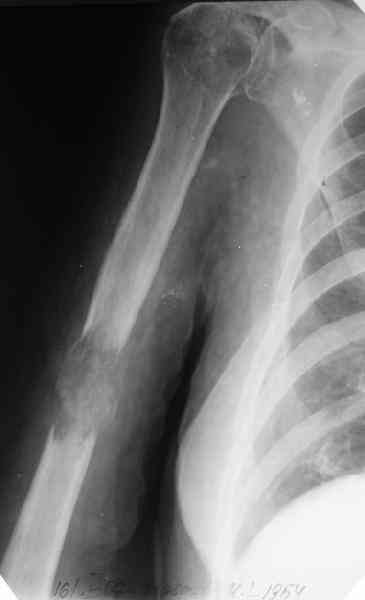

Женщина 53 лет получила патологический перелом правого плеча в

феварле, и левого в марте - mts из невыясненного первичного очага.

На нас вышли родственники. Состояние пациентки уже не очень, анемия

(Hb -50-60 г/л), исхудалв, но асцита нет, в легких чисто. Поскольку

женщина совершенно беспомощна, решили сделать остеосиннтез.